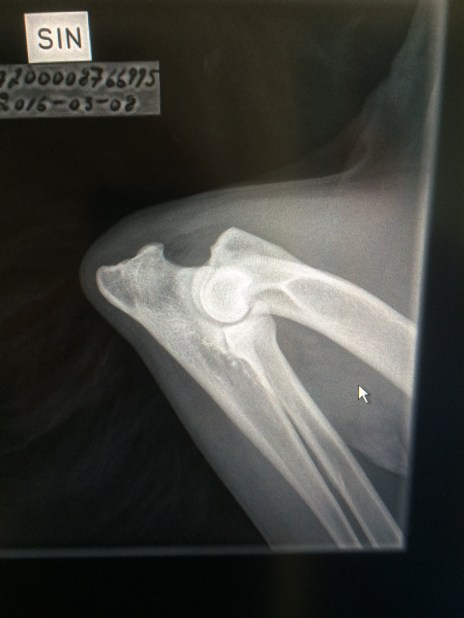

Idag har vi röntgat Mimmis armbågar för officiell avläsning ! Väntar med spänning på vad SKK säger. Passade på att kika på höfterna också !